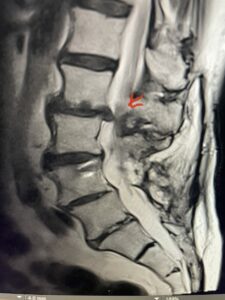

Fig 1b: axial T2-weighted MRI demonstrating severe lumbar stenosis (red arrow)